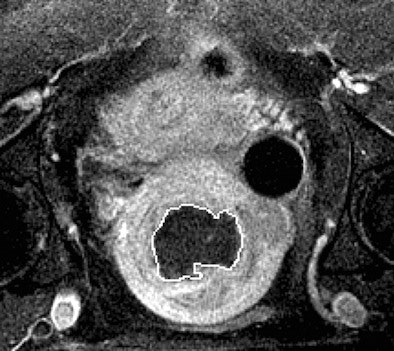

| Above, T2-weighted axial MR image of a hypointense fibroid in a 42-year-old patient before MR-guided focused ultrasound surgery. Below, T1-weighted gadolinium-enhanced axial MR image of the same fibroid immediately after treatment. The outlines of treated fibroid and NPV were contoured with electronic calipers to compute the area per section by using volumetric analysis software. |